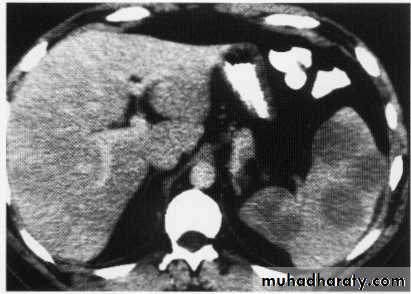

hepatic mets

hepatic mets,arterial phase

hepatic mets venous phase

Hepatic mets.